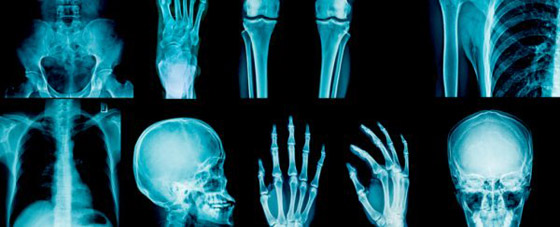

بدأ الأمر عندما ذهبت إحدى أفراد أسرة مارسيلي للطبيب، وهي الجدة على وجه التحديد، حيث كانت تشكو من أزمة ظنت أنها بسيطة في عظام الكاحل، لتفاجأ بعد إجراء الأشعة أنها تعاني من كسر في تلك المنطقة ولم تشعر به، ما فتح المجال لإجراء دراسة طبية على أفراد الأسرة جميعا، بعدما اتضح كونها عائلة لا تشعر بالألم بدرجات مريبة.

توصل الباحثون إلى أن الخلل الذي يمنع الأعصاب من الإحساس بالألم بدرجات طبيعية، يبدو ممثلا في غياب جين يدعى ZFHX2، ما تم اكتشافه من خلال فحوصات DNA حمض نووي طويلة، أجريت على أفراد الأسرة جميعا بلا استثناء، كما قام الباحثون بإزالة الجين نفسه من فئران التجارب، ليلاحظوا فيما بعد أن الفئران صاروا لا يشعرون بالألم، تماما مثلما يحدث لأسرة مارسيلي الإيطالية.